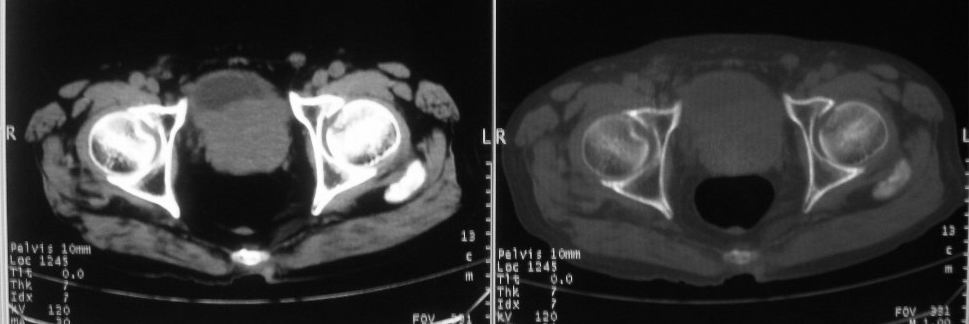

以下是引用zjzjr在2008-10-3 12:59:00的发言:[br]前列腺癌伴左髂骨\\腰椎转移可能性大.

以下是引用卜一在2008-10-3 13:40:00的发言:[br]前列腺癌!左髂骨\\腰椎转移?建议行全身骨扫描!

以下是引用深泽交通医院在2008-10-3 15:33:00的发言:[br]前列腺实性增大伴分叶状,与包膜间隙境界不清;椎体松质区间结节样密度影,考虑:前列腺癌,并椎体成骨性转移